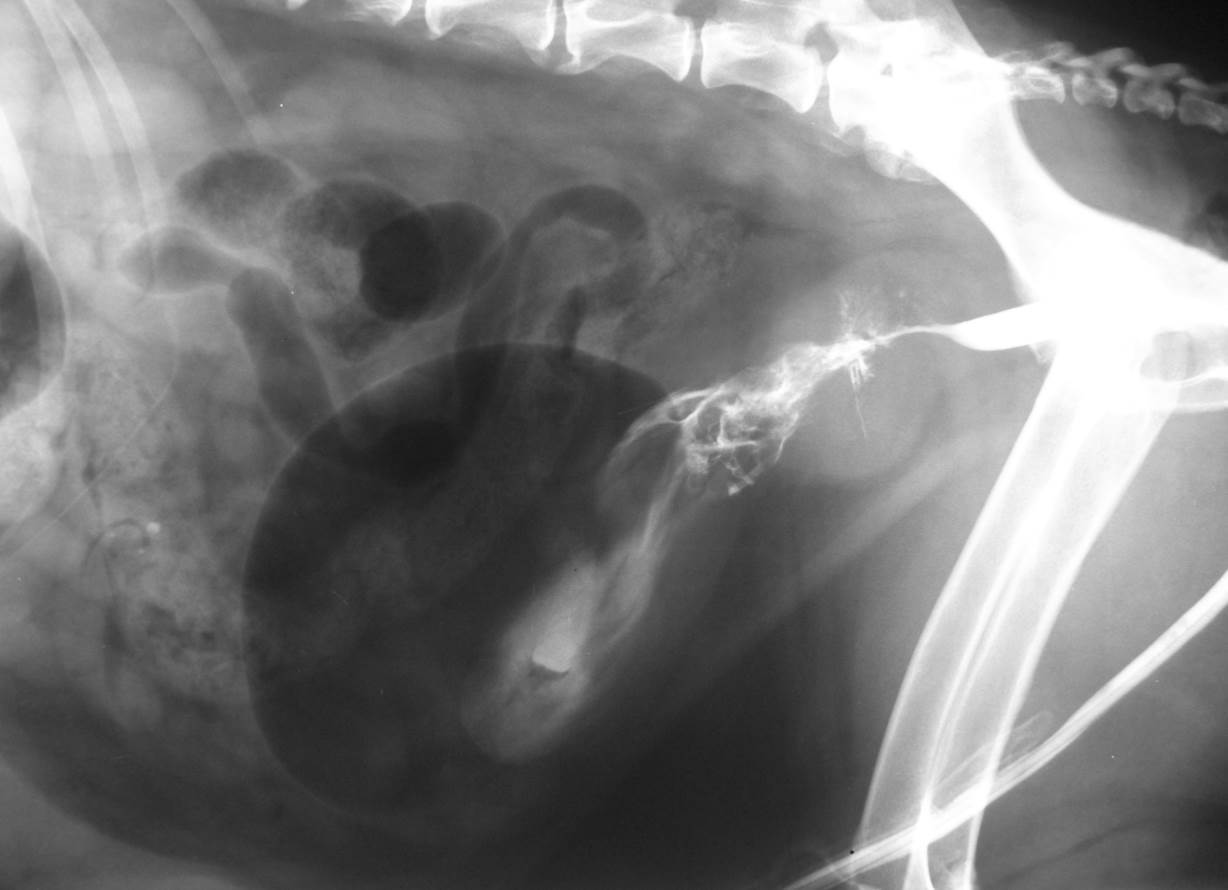

Case Joss

Discuss this case?

–catheter biopsy hopefully to confirm a benign/inflammatory lesion

–focus on identifying a UTI and managing with a prolonged course of antibiotics (?6-8 weeks minimum)

–surgical curettage of the bladder

What is Polypoid cystitis?

Polypoid cystitis is a rare disease of the urinary bladder in dogs characterized by inflammation, epithelial proliferation, and development of a polypoid mass or masses without histopathologic evidence of neoplasia.

Where are most of the masses found in polypoid cystitis?

Most of the masses (11/14) were located cranioventrally in the bladder as opposed to transitional cell carcinoma, which has a predilection for the bladder neck or trigone area. It is unknown whether persistent or recurrent UTI predisposes to polyp formation or if polyps predispose to UTI.